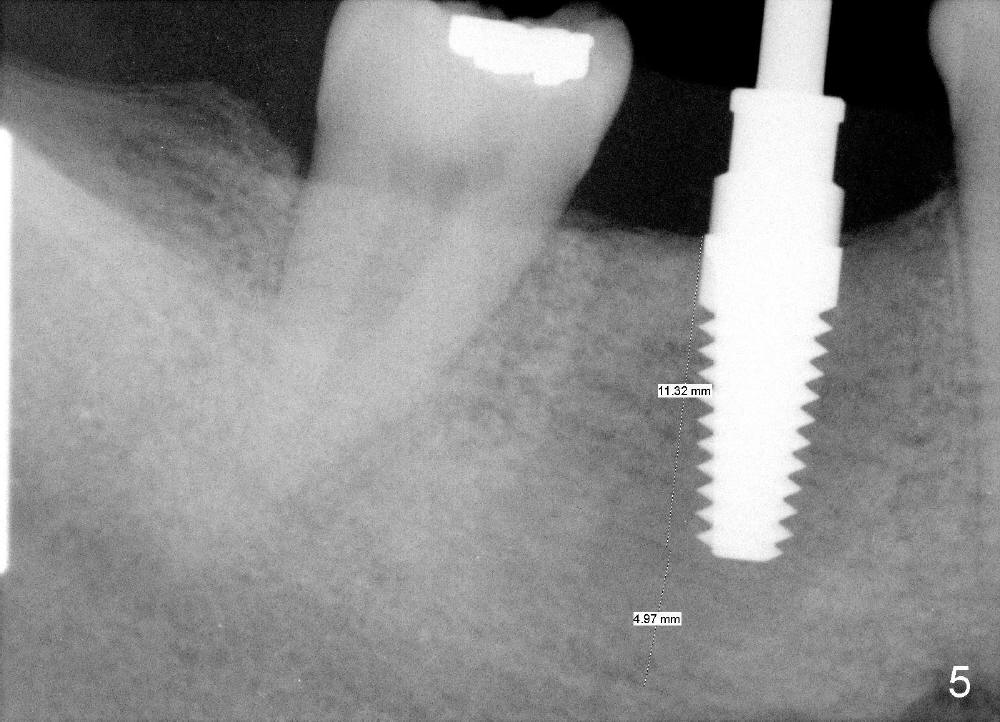

An incision is made instead of flapless, the socket is found to be filled with regenerated bone (Fig.3). After using 2 mm pilot drill, a paralleling pin is inserted to confirm trajectory and distance from the inferior alveolar nerve (Fig.4). Osteotomy is enlarged by Bicon reamers; threads are formed by insertion of Tatum 5x14 mm tap at the depth of 11 mm (Fig.5). The threads are visible when the tap is removed (Fig.6 ^). The advantage of using tap(s) is to test binding to the bone. If the tap is loose, the next sized tap should be used before placing a proper sized implant. This step is particularly critical when placing a large immediate implant or when the socket is immature.